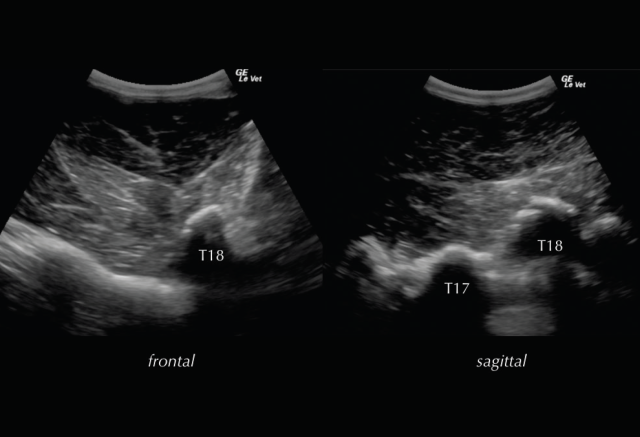

Deep to the ligament the fibrocartilaginous cap, visualised as a hypoechogenic line of approximately 1mm, is visible and runs parallel to the hyperechoic line of the DSP bone surface. The ISS cannot be assessed fully and a statement about potential iminging DSPs should not be made based on ultrasonography alone. The intervertebral articulations can be examined ultrasonographically, both in sagittal and frontal planes, using a convex transducer (Denoix 1999a; Reisinger and Stanek 2005).

The anatomy and ultrasonographic appearance of the joints change slightly from cranial to caudal. The mammillary process is more prominent in the thoracic spine and the joint is positioned further axial and closer to the DSP compared to the lumbar region. Signs of pathology in the intervertebral articulations (see Figure 4) include new bone formation and an enlarged outline of the facet (Denoix and Dyson 2003).